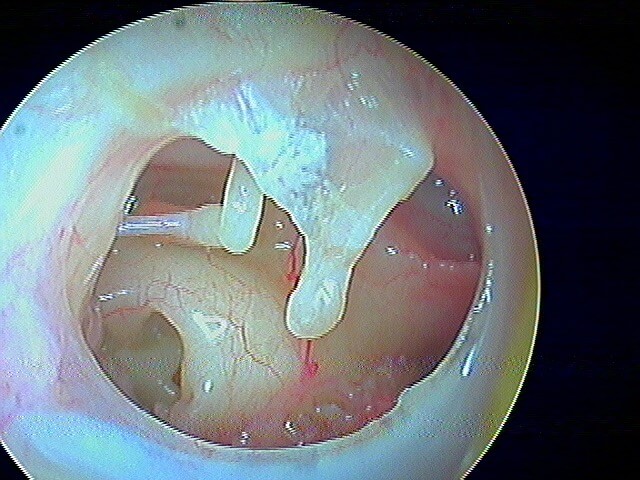

2/7 corps étrangers du CAE

De toutes formes et constitutions (et pas que chez l'enfant! L' aïl est fréquen chez l'adulte!): ici une perle. Je les enlève à la micro-pince/crochet avec une lumière frontale. Chez les enfants, quand je n'y arrive pas, j'utilise l'irrigateur d'eau (notamment une fois pour un pois chiche!).

Après abaltion, le tympan est non perforé non infecté.

Ici le tympan est perforé et infecté après ablation de cette boucle d'oreille, chez un·e adulte.

Encore une perle: